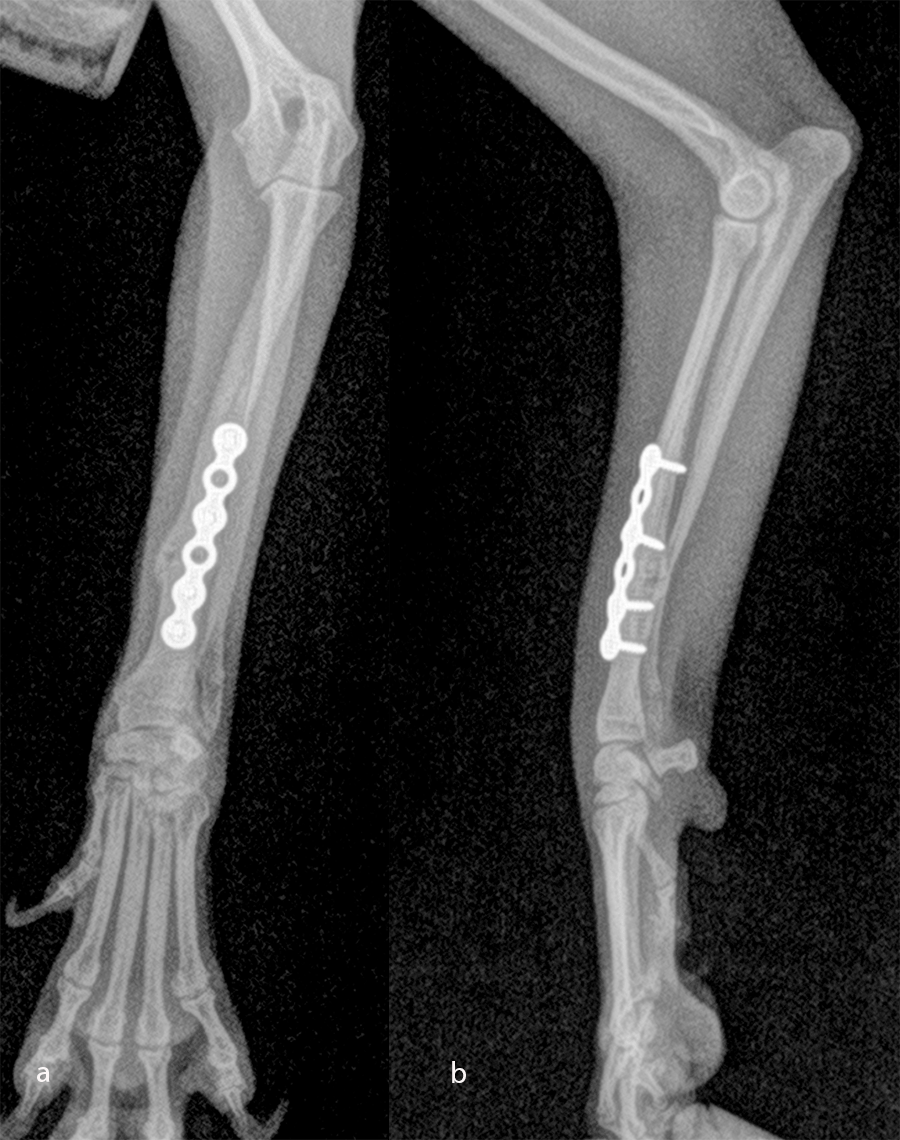

Open reduction and internal fixation of distal radial and ulna fractures with a 1.3 radial plate and a 1.3 ulnar plate (Fig 10).

The patient was a 2.5-month-old, 1 kg Japanese Spitz dog presenting with a radial-ulna fracture of the left thoracic limb after a jump from the sofa. The LCP 1.3 T-plate was perfectly adapted for the distal radial fracture. As the dog was "active" and as the ulna was about the same size as the radius (Fig 11), a four-hole LCP 1.3 adaptation plate was used on the ulna.

An open but do-not-touch approach was performed, and the plate was fixed with both cortex screws and locking screws for both plates (Fig 12). After 4 months, the fractures were totally healed with normal bone growth and the dog had a complete functional recovery (Fig 13).